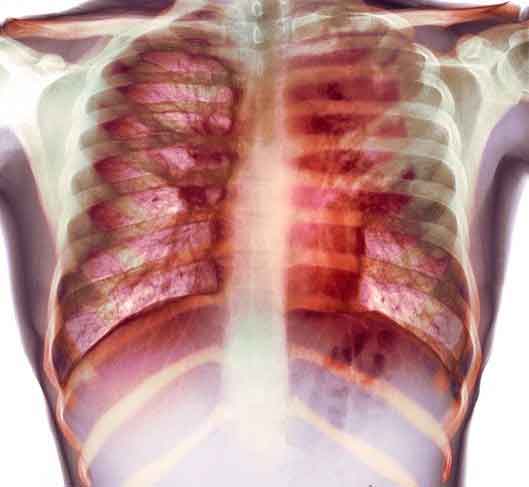

Alte dosi di vitamina D aiutano i pazienti con tubercolosi a recuperare piu’ rapidamente. A dirlo, uno studio della Queen Mary, University of London, pubblicato sulla rivista ‘Proceedings of the National Academy of Sciences’. I ricercatori hanno mostrato per la prima volta che alte dosi di vitamina D, date in aggiunta agli antibiotici, inducono una migliore risposta immunitaria nei pazienti con tubercolosi. I risultati indicano che la vitamina D puo’ affievolire la risposta infiammatoria all’infezione, aiutando i pazienti a recuperare piu’ velocemente e con meno danni per i propri polmoni.

Inoltre, gli scienziati ritengono che l’integrazione della vitamina D possa aiutare anche in casi di polmonite. Gli scienziati hanno coinvolto 95 pazienti tubercolotici che ricevevano un trattamento antibiotico standard dividendoli in due gruppi: a 44 hanno dato alte dosi di vitamina D mentre i restanti 51 hanno ricevuto un placebo.

Il batterio della tubercolosi scompariva completamente dal sangue dei pazienti che avevano ricevuto la vitamina D in, mediamente, 23 giorni: 13 in meno rispetto ai pazienti che avevano assunto il placebo.